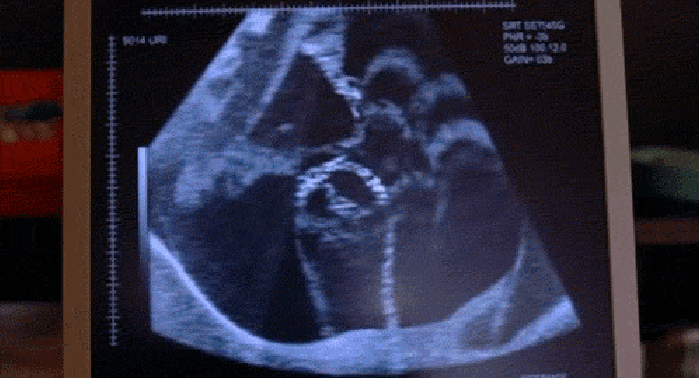

新生儿神经管缺陷

▼